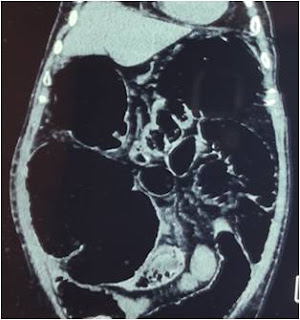

An elderly male with history of weight loss and progressive constipation presented to emergency room. He was a known diabetic and had undergone coronary bypass 1 year ago had low ejection fraction (35%). Abdominal CT scan is provided in Figure 4. The total white blood cell count was 39,000 mm3

Figure 4. Closed loop obstruction of large bowel with hugely distended cecum

At surgery, there was an obstructing mass lesion in sigmoid colon with infiltration of dome of urinary bladder. The cecum appeared gangrenous. A subtotal colectomy with partial cystectomy was performed. Reconstruction was by an ileorectal anastomosis with diverting loop ileostomy. He had an uneventful postoperative recovery and was discharged on 8th postoperative day. The biopsy reported adenocarcinoma sigmoid colon T4N1 with all clear surgical margins. The ileostomy was successfully reversed 8 weeks later.